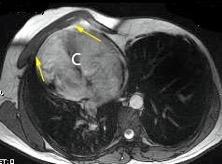

Tumor desmoide (“Fibromatosis agresiva”)

T1: Isointensos con músculos.

T2: Señal intermedia y de alta intensidad.

Presencia frecuente de áreas curvilíneas y lineales dentro de la lesión

Mansour J et al. Diagnostic and Imaging Approaches to Chest Wall Lesions. Radiographics 2022